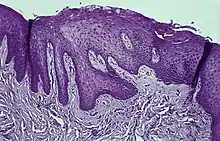

Histology

Fig.3. Hematoxylin Eosin staining of the attached gingiva with a Retrocuspid papilla.

Immunohistochemical staining with FXIIIa [9] antibody disclosed a population of reactive spindle- or stellate-shaped cells[10] in 11 of 15 cases, located in connective tissue papillae and in a few cases also distributed throughout the lesion. The FXIIIa-stained cells appeared together with the frequently observed stellate, "young" occasionally multinucleated fibroblastic cells observed in more than 50% of patients aged 10–69 years. It is likely that FXIIIA-expressing "mucosal dendrocytes" are pathologically involved in some way.[11][12][13]